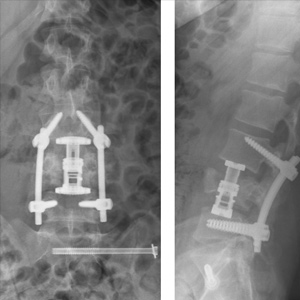

Spinal stenosis (Lumbar) Spinal stenosis (Cervical) Spinal stenosis (Thoracic) Lumbar Disc Herniation Spondylolisthesis Cervical Foraminal Stenosis Vertebroplasty Lumbar Fusion Anterior Cervical Fusion (ACDF) Posterior Cervical Fusion Thoracic Fusion Revision Lumbar Fusion Surgery Facet Joint Cyst Spinal Tumour Minimally Invasive Lumbar Fusion (XLIF) Minimally Invasive Lumbar Fusion (ALIF) Lumbar Fusion (TLIF) Thoraco-lumbar Fusion Lumbar Corpectomy Complex Lumbar Spine Surgery (Spino-pelvic fixation) Complex Cervical Spine Surgery Complex Thoracic Spine Surgery Occipito-cervical Fusion Minimally invasive surgery for thoracic disc herniation Other Related Topics